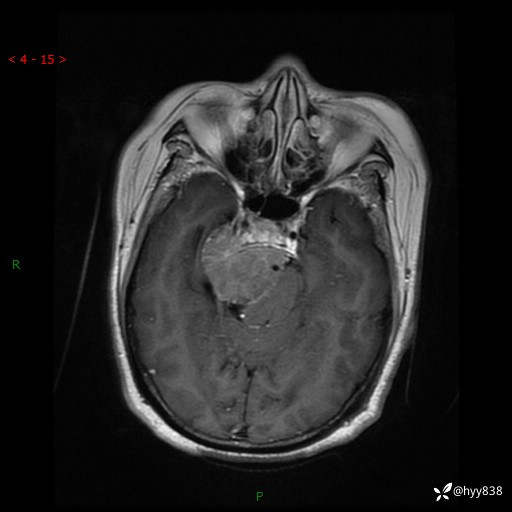

颅脑CT平扫